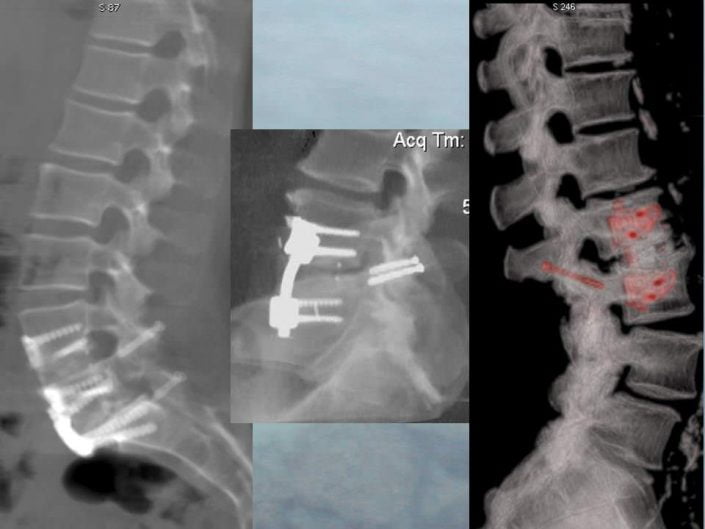

L’ensemble de la progression est toujours suivi sous double contrôle scopique et scannographique.

Une vis creuse autoforeuse Stryker© Asnis III de 4 millimètres de diamètre et dont la longueur précise est calculé sur le scanner peropératoire est introduite le long de la broche, transfixie les articulaires postérieures et se termine dans le pédicule vertébral en cas de trajet transfacettaire.

Nous avons démontré la faisabilité de cette nouvelle technique percutanée en utilisant le double contrôle scopique et scannographique.

La comparaison des résultats obtenus sur le trajet des vis sur notre série par rapport aux techniques chirurgicales classiques est très satisfaisante puisque toutes les vis sauf une (38 vis sur 39) ont été placées avec succès selon les critères chirurgicaux.

Ces résultats sont au moins comparables à ceux de la littérature sur le placement des vis transfacettaire selon la technique chirurgicale classique à ciel ouvert et sous anesthésie générale.

Aucune complication iatrogène n’est à déplorer en particulier neurologique ou vasculaire ; le champ de visualisation dans les 3 plans de l’espace obtenu par le scanner et la scopie sécurise la progression du matériel d’ostéosynthèse et facilite le positionnement optimal des vis.